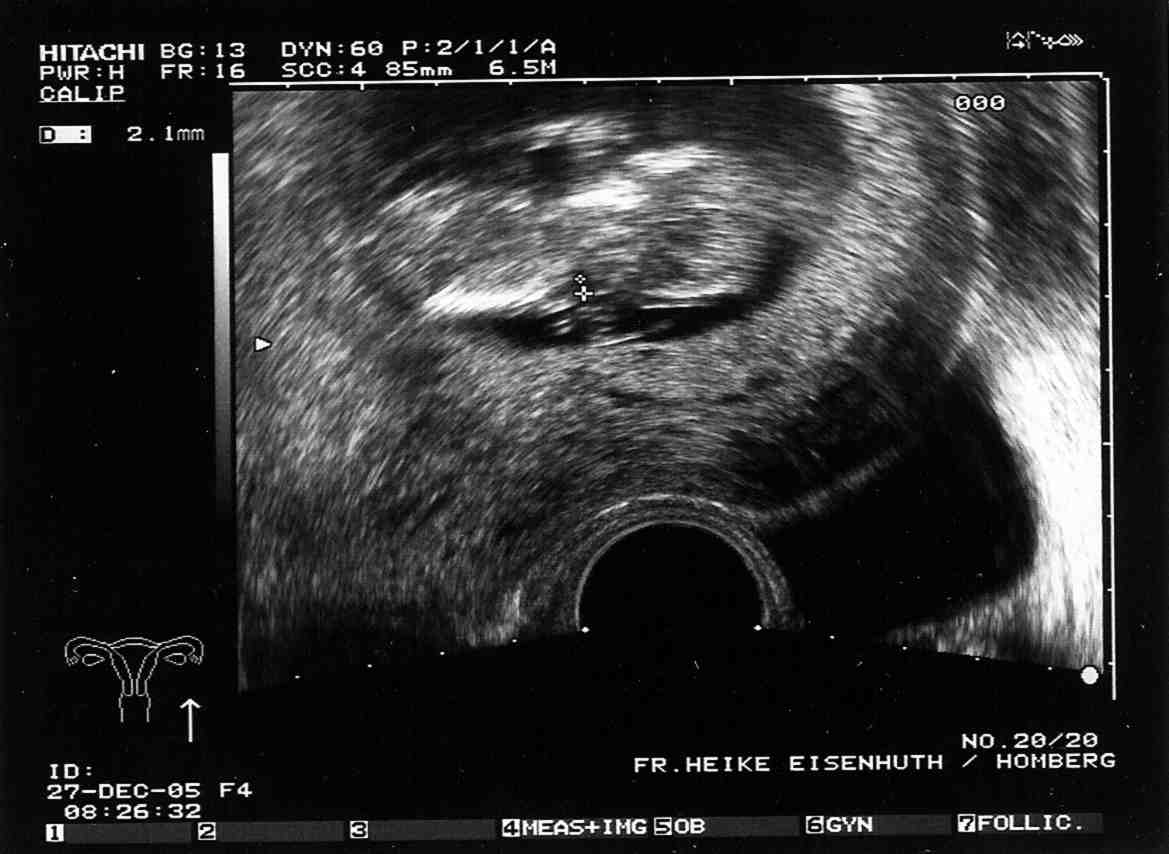

so.... ich hab mir grad in der Mittagspause mal Tanja´s Mutterpass gestohlen und die letzten Bilder eingescannt.

US-Bild vom 27.12.2005